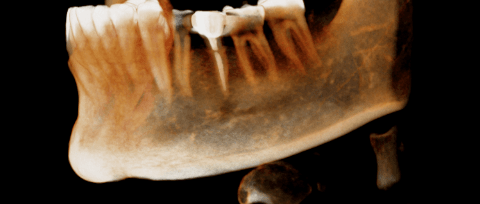

左下第一二大臼齒有膿包周囊袋過深,發現牙根斷裂 即拔即種當下清除發炎組織再補骨促進骨整合 左半邊咬合